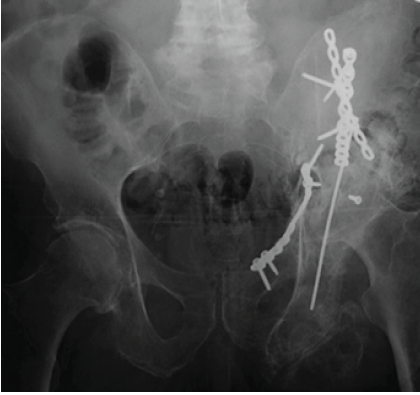

In the interval he had residual pain, limb-length discrepancy, weakness of left lower extremity, hip flexion contracture, low back pain, and foot drop. Neurosensory examination and films taken in the interval and in the pre-operative period were consistent with initial findings and significant for non-union of the left acetabular fracture. 14 months s/p ORIF X-ray was significant for non-union of acetabular fracture (Fig. 2), no imaging was taken in the interval to assess for lumbar pathology.

Figure 2: Anterior-posterior X-ray film significant for left acetabular non-union 14 months s/p open reduction and internal fixation.